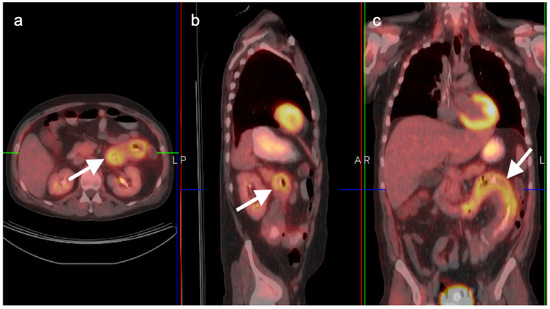

9. Bowel Adenocarcinoma: Colon, Rectum, Small Bowel